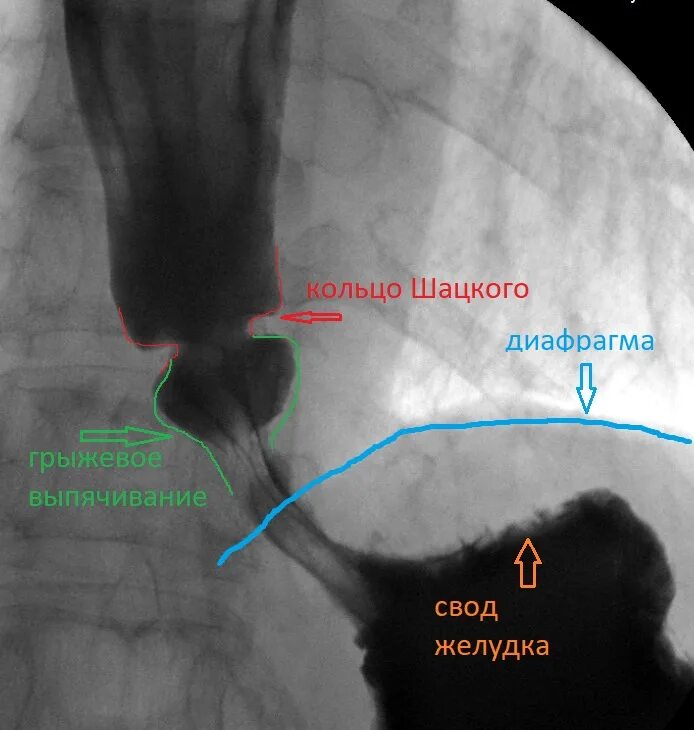

Кольцо шацкого в пищеводе что это